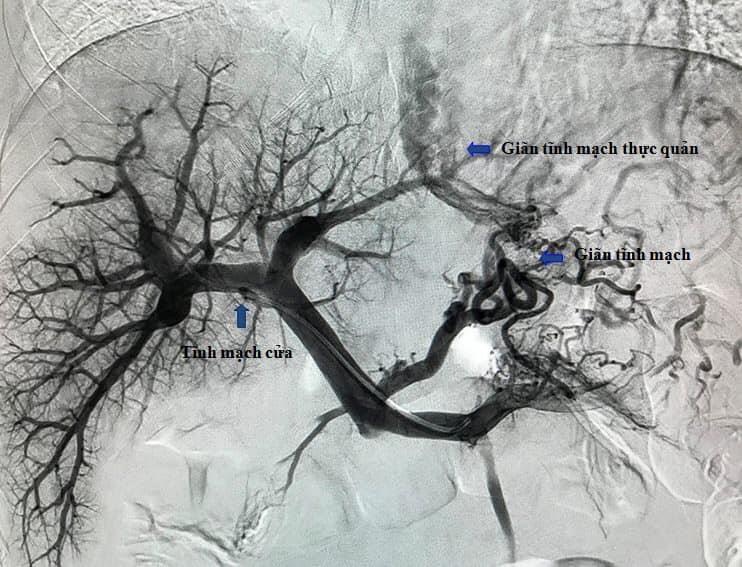

| Hình chụp hệ tĩnh mạch cửa và các búi giãn tĩnh mạch thực quản của bệnh nhân. Ảnh: BVCC. |

Lúc này, ê-kíp điện quang can thiệp đã được mời hội chẩn cấp cứu và chỉ định làm kỹ thuật tạo luồng thông cửa chủ trong gan qua da (TIPS). Đây là kỹ thuật đặt một giá đỡ kim loại có màng phủ trong gan, tạo một dòng chảy trực tiếp từ tĩnh mạch cửa lên tĩnh mạch gan làm giảm áp lực tĩnh mạch cửa, kết hợp với nút các búi giãn tĩnh mạch thực quản để cầm máu.